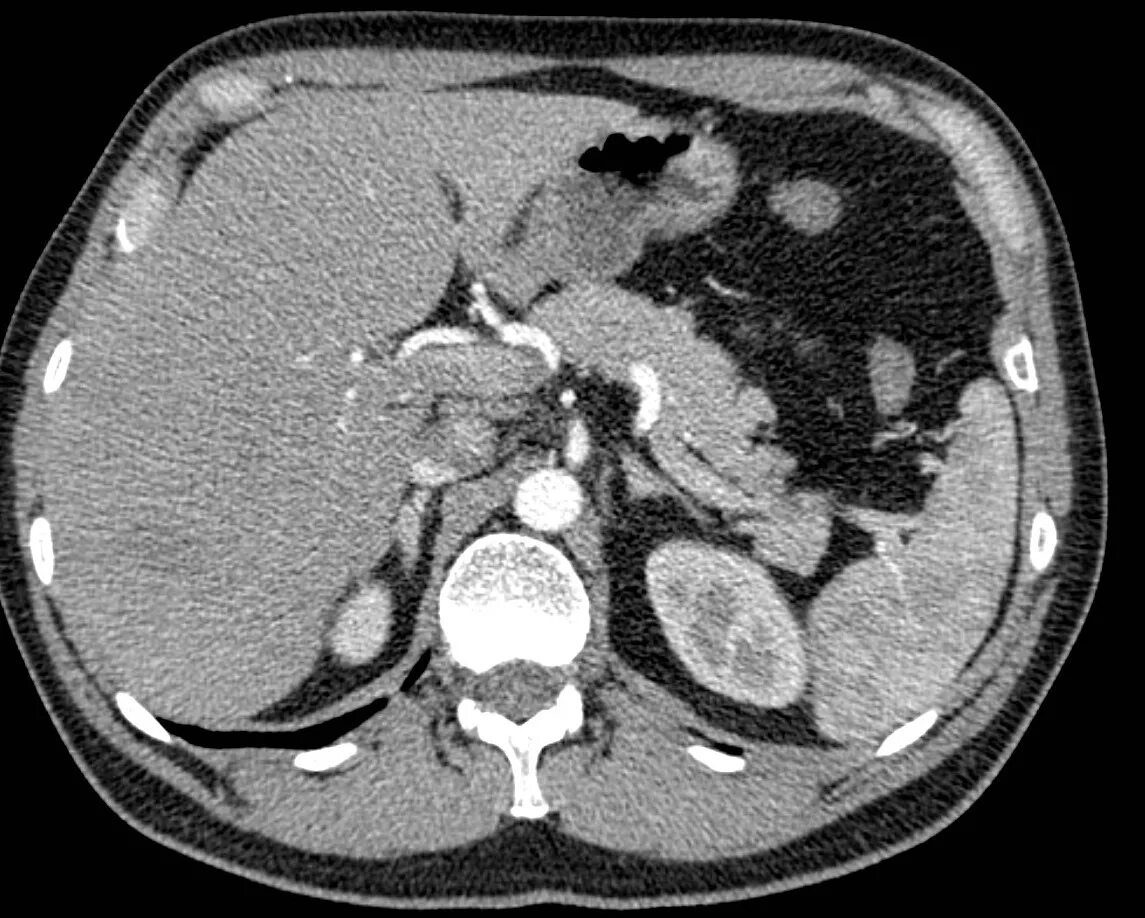

Образования печени кт